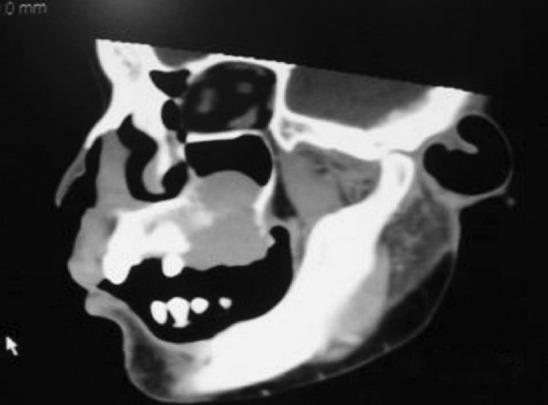

Non-Hodgkin's lymphomas are a group of neoplasms that originate from the cells of the lymphoreticular system. Forty percent of non-Hodgkin's lymphomas arise from extra nodal sites. Non-Hodgkin's lymphomas detected primarily in the bone are quite rare, but among jaw lesions, they are more frequently present in the maxilla than in the mandible. There are no classical characteristic clinical features of lymphomas involving the jaw bones. Swelling, ulcer or discomfort may be present in the region of the lymphoma, or it may mimic a periapical pathology or a benign condition. Extranodal non-Hodgkins lymphoma of the maxilla could present as one of the early manifestation of detrimental diseases. Clinically these types of lymphoma can mimic an inflammatory endo-periodontal lesion with symptoms of pain and local discomfort. The greater the delay in diagnosis subsequently worsens the prognosis. A case of maxillary non-Hodgkin's lymphoma with an unusual presentation is discussed.

非霍奇金淋巴瘤是一组起源于淋巴网状系统细胞的肿瘤。40%的非霍奇金淋巴瘤起源于结外部位。主要在骨骼中检测到的非霍奇金淋巴瘤非常罕见,但在颌骨病变中,它们在上颌比在下颌更常见。累及颌骨的淋巴瘤没有典型的特征性临床症状。淋巴瘤区域可能出现肿胀、溃疡或不适,也可能类似根尖周病变或良性疾病。上颌结外非霍奇金淋巴瘤可能是有害疾病的早期表现之一。临床上,这些类型的淋巴瘤可表现为炎性牙髓牙周病变,伴有疼痛和局部不适症状。诊断延迟越久,预后越差。本文讨论了一例表现不寻常的上颌非霍奇金淋巴瘤病例。